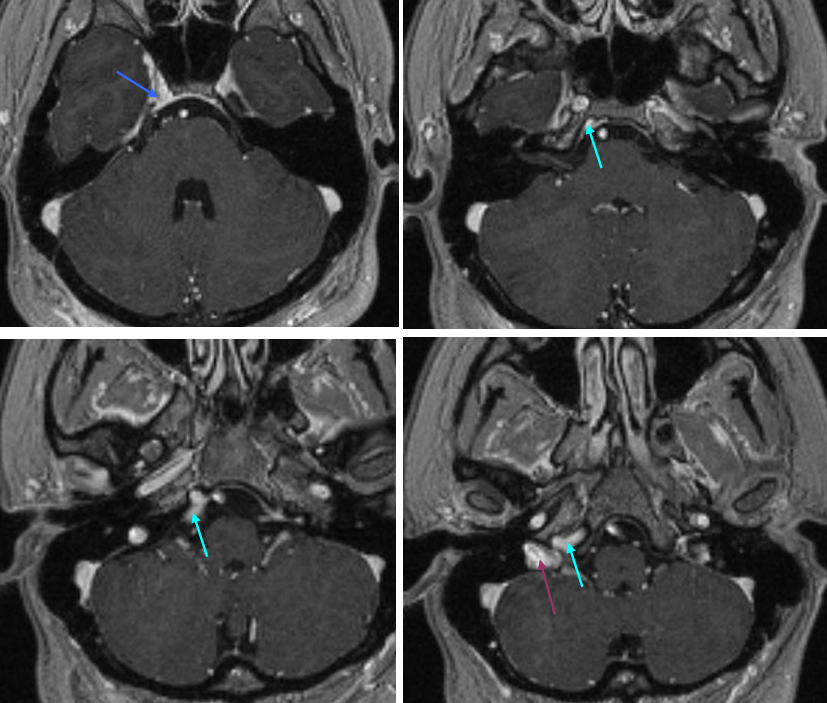

Inferior Petrosal Sinus MRI — some cross-sectional imaging to help identify sinus outflow pathways; inferior petrosal sinus extends along the lateral aspect of the dorsum sella towards the jugular foramen.

Cavernous Sinus=blue; inferior petrosal sinus=light blue; sigmoid sinus=purple

The inferior sagittal sinus is highly variable in extent of development and course. This one (light blue) has an unusual craniocaudal orientation. Notice complete lack of cavernous sinus capture by the sylvian veins, which drain instead towards the sigmoid region.

Labbe=dark blue. Inferior temporal vein=beige. Inferior sagittal sinus=light blue. Straight sinus=black. Basal vein=red. Internal Cerebral Vein=green. Notice dominance of drainage to the sigmoid sinus system with no visualization of the sphenoparietal sinus or cavernous sinus. The basal vein drains exclusively posterior. This patient would be very unlikely to tolerate sigmoid sinus or straight sinus thrombosis.